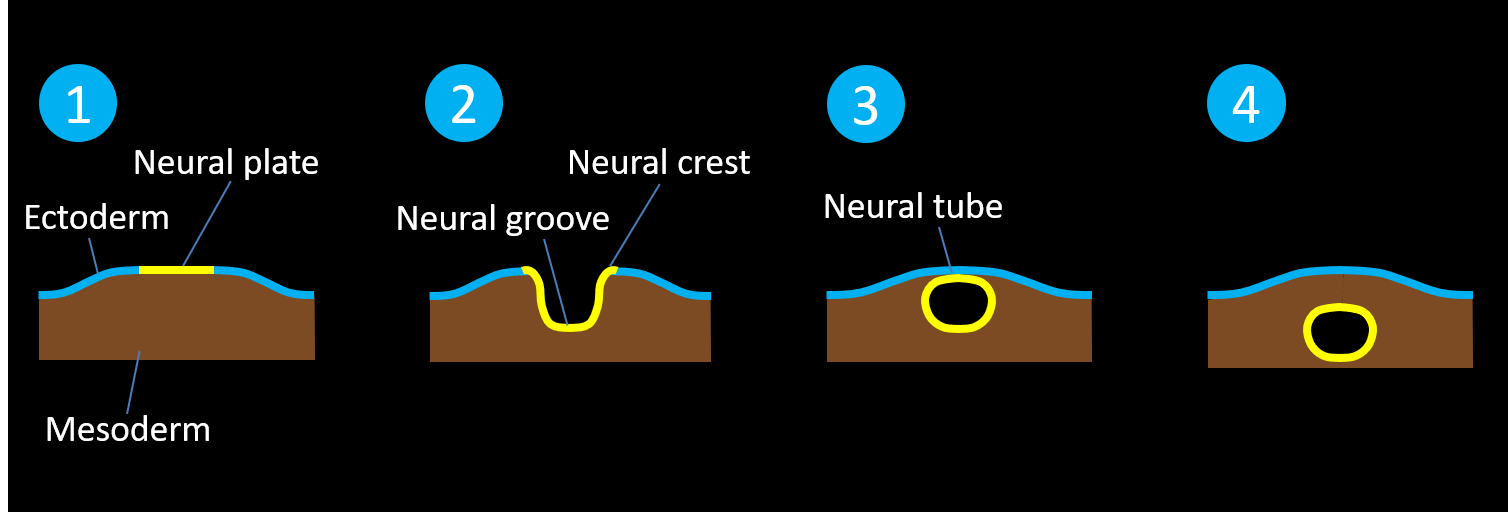

- Try thinking about them in groups of conditions resulting from failures of different steps of neurulation (see below diagrams):

- Normal neurulation occurs during the third and fourth weeks of gestation as the neural tube forms within and then separates from the ectoderm

-

-